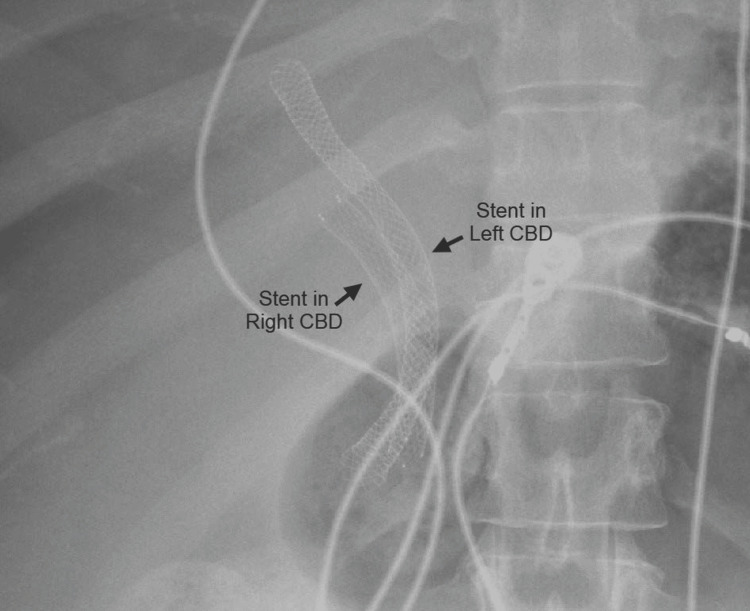

Abdominal computed tomography (CT) with IV contrast showed multiple peripherally enhancing masses within the liver, as well as bilateral intrahepatic biliary ductal dilation (Figure 1). Endoscopic ultrasound revealed multiple large solid masses in the liver consistent with metastases and excluded a fluid component, i.e., abscess. Due to the acute cholangitis, endoscopic retrograde cholangiopancreatography (ERCP) was performed, and the PTC drain was visualized emerging from the major papilla. The common bile duct was then cannulated using a balloon adjacent to the PTC drain, and contrast was injected. The cholangiogram showed a normal CBD and a mild stricture in the common hepatic duct, but the PTC drain was in an entirely separate ductal system (Figure 2A). A metal stent was then placed into the CBD and extended from the common hepatic duct to the major papilla (Figure 2B). The metal stent emerged from the major papilla adjacent to the PTC drain (Figure 3). Due to concern about the misplacement of the PTC drain, the interventional radiology (IR) team interrogated the drain using contrast (Figure 4). This revealed the presence of a DCBD, with the PTC drain placed in the right CBD and an endoscopically placed metal stent in the left CBD. Consecutive images from the contrast study showed a single proximal communication between the two CBDs. The IR team then removed the PTC drain, and a metal stent was placed in the right CBD, with both stents joining at the major papilla, thus confirming the presence of type Vb DCBD (Figure 5). Following the placement of both metal stents, the patient’s serum bilirubin levels normalized, and symptoms improved to where she was safely discharged home to continue her palliative chemotherapy regimen with her oncologist. Upon following up with her oncologist, her serum bilirubin was 1 mg/dL. The patient ultimately elected to pursue home hospice care shortly afterward.

As evidenced by Figure 5, our patient had a type Vb DCBD as there were two separate extrahepatic bile ducts with a single proximal communicating channel that both had common drainage into the duodenum. As mentioned earlier, there are only two other cases of type Vb DCBD reported thus far [ref. 8,ref. 9]. Both cases involved older female patients, 81-years-old and 44-years-old, respectively, who both presented with cholangitis due to choledocholithiasis [ref. 8,ref. 9], unlike our case where she presented with cholangitis due to cholangiocarcinoma causing biliary obstruction.